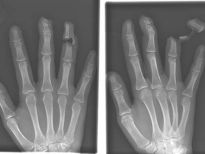

Bu röntgenler gerçek!

Bu röntgenler gerçek! galerisi resim 1